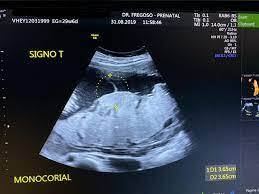

Aspectos ultrasonográficos a tomar en cuenta durante la evaluación de la corionicidad de embarazos múltiples

• Signos “Lambda” (bicorial) o de la “T” (monocorial)

Corresponde a la ausencia de tejido palcentario entre las membranas fetales e implica que existe un embarazo donde la placenta está compartida (monocorial)

Signo de la T